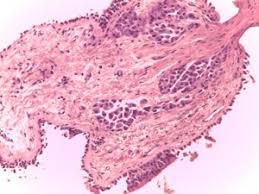

- Biopsia pulmonar: Recoger una muestra de tejido pulmonar mediante punción con aguja gruesa transbronquial o a cielo abierto para confirmar el diagnóstico anátomo-patológico.

Linfangitis carcinomatosa. Invasión de los vasos linfáticos pulmonares por células neoplásicas o cancerosas, bloqueando así el flujo normal de la linfa e invadiendo el tejido conectivo contigüo de forma difusa. Se puede considerar como una forma peculiar de metástasis pulmonares. Es relativamente infrecuente, pues tan sólo se ve en un 6-8% de los pacientes oncológicos. Esto puede ocurrir debido a muchos tipos de cáncer, pero los más frecuentes son el cáncer de mama (33%), pulmón (17%), colon, estómago (29%), páncreas (4%), tiroides y próstata (3%).

Afección por la que las células cancerosas se diseminan desde el tumor original (primario) e invaden los vasos linfáticos (tubos delgados que llevan la linfa y los glóbulos blancos a través del sistema linfático del cuerpo). Los vasos linfáticos invadidos se llenan luego de células cancerosas y quedan bloqueados.